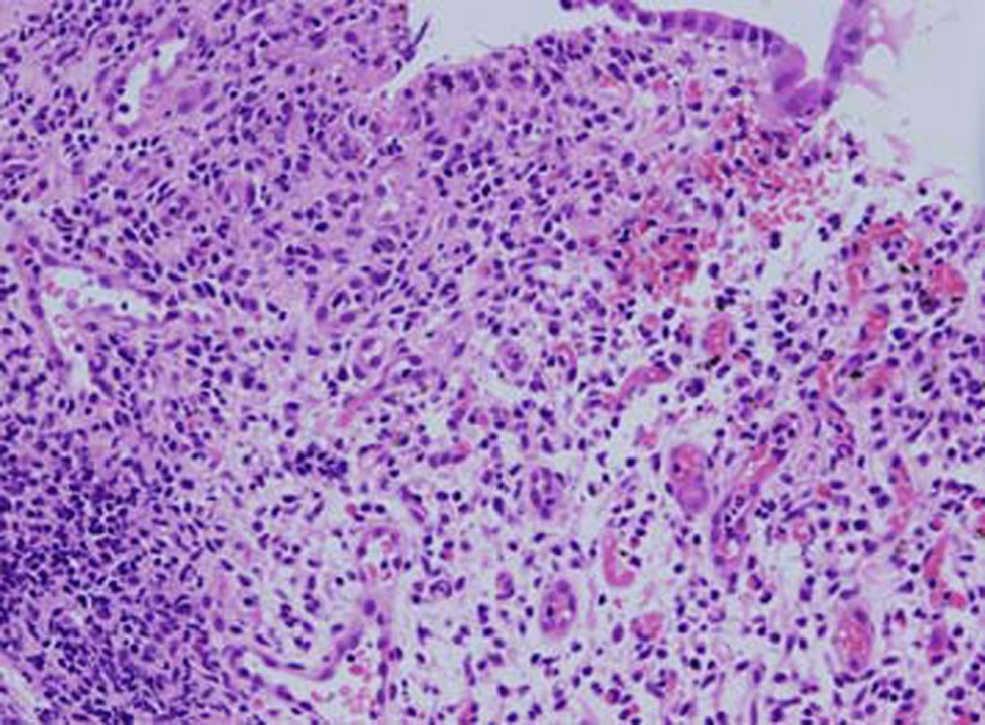

Ante la evidencia de hemorragia digestiva, se realizó estudio endoscópico con el hallazgo de una mucosa gástrica edematosa, eritematosa y friable y una mucosa duodenal igualmente friable. En la colonoscopia se observó una mucosa petequial y eritematosa sin lesiones ulcerosas que afectaba de manera continua a todo el marco cólico. El estudio histológico de las muestras recogidas puso de manifiesto en todas las localizaciones una mucosa con marcada inflamación aguda y crónica con intenso daño epitelial (fig. 1). Ante la sospecha de infección vírica, se realizó determinación de ácido desoxirribonucleico (ADN) de CMV en mucosa colónica con la técnica de PCR (polymerase chain reaction‘reacción en cadena de la polimerasa’) que fue positiva para CMV y negativa para virus varicela zóster (herpes simple 1 y 2), virus Epstein-Barr y virus herpes 6.

Figura 1. Mucosa colónica con daño epitelial intenso e infiltrado inflamatorio agudo y crónico muy marcado indicativo de infección por virus.